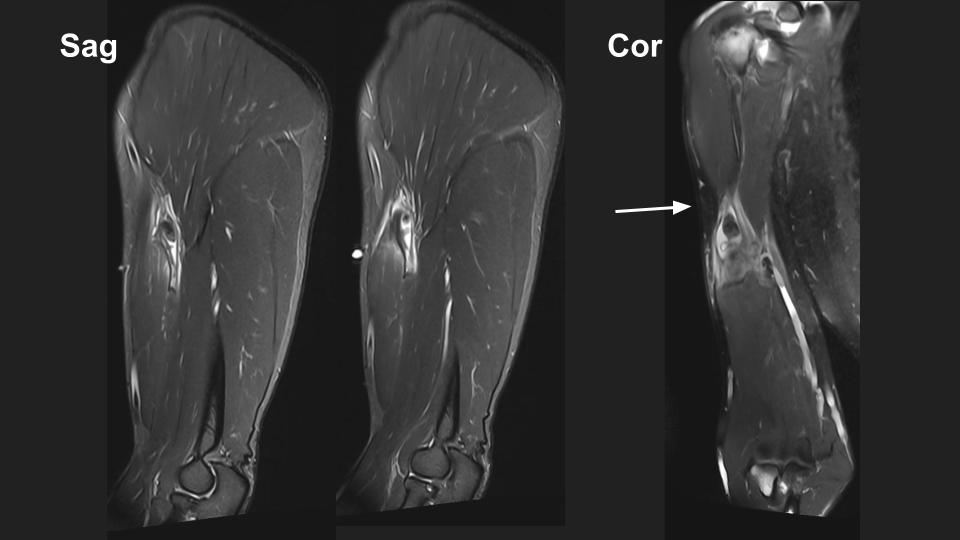

58M shoulder and upper arm pain x 4 weeks

There is a complete tear of the intraarticular long head biceps tendon (LHBT). The intraarticular remant is displaced into the superior subscapular recess and the torn retracted tendon is distal to the pec major insertion (bue arrow) in the mid upper arm (white arrow). Note the delaminating tear of the subscapularis tendon (red arrow). There is moderate supraspinatus tendinosis without tear (not shown).